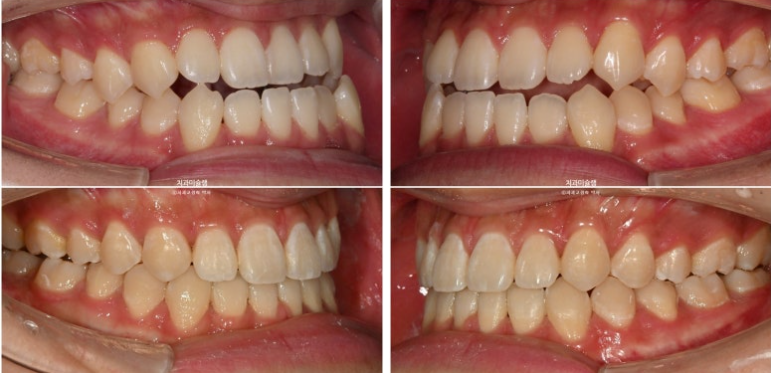

중심선이 어긋나있고 앞니 개방교합이 보입니다.

주걱턱으로 인해 앞니가 거꾸로 물리는 반대교합이 있습니다.

어금니 교합관계도 심한 3급입니다.

중심선은 정확히 맞으며 개방교합은 충분히 해소되었습니다.

반대교합은 개선되었고 교합관계는 1급을 달성

이제 전후 비교 보겠습니다.

23.06~26.01